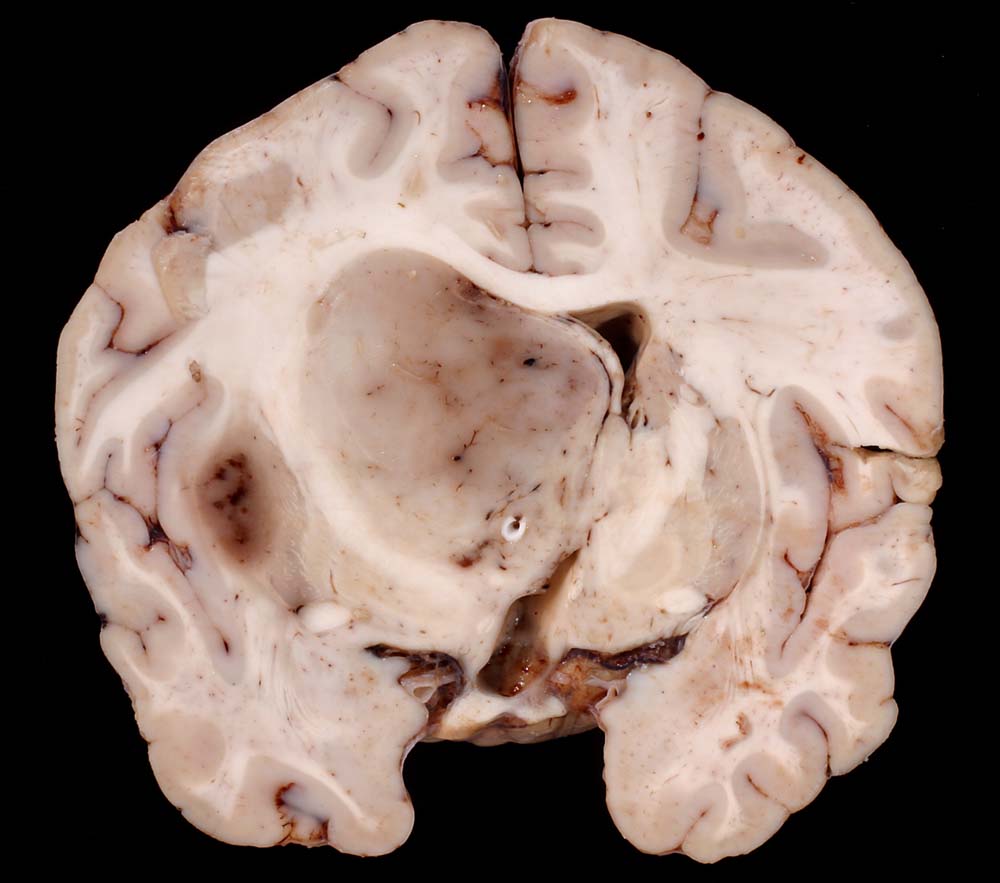

Anaplastisches Oligodendrogliom

Gräuliches Tumorgewebe verschiebt die Mittellinie stark zur Gegenseite und komprimiert den Seitenventrikel.

Anaplastisches Oligodendrogliom Grad III nach WHO.

Thalamus-Tumor. Hydrocephalus bei Tumoreinblutung. Einklemmung.